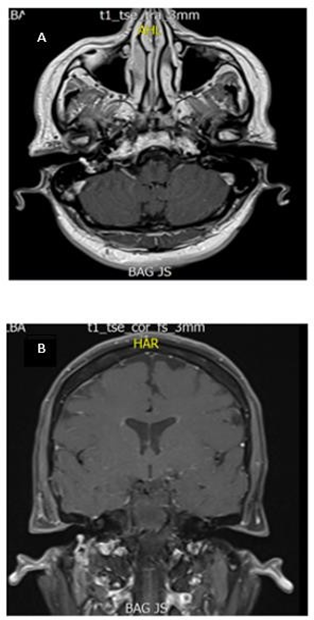

Figure 2 A-B. Axial slice of MRI T1- contrast sequence: Hyperintense lesion involving part of the right EAC. B. Coronal slice of contrasted MR T1 sequence: Hyperintense lesion involving the stylomastoid foramen and right facial nerve.

Magnetic resonance imaging of the brain and neck showed a hypervascular lesion, hyperintense in all sequences involving the stylomastoid foramen and part of the right EAC. Transcanal biopsy showed multiple thin-walled vascular channels with a hemangiopericytoma pattern and crowded cells with scant cytoplasm and ovoid nuclei in the periphery. Immunohistochemical studies were positive for chromogranin and synaptophysin for the diagnosis of paraganglioma. Next, the patient was taken to surgery for resection of the tumor via retro auricular approach with extension to the cervical region and simple mastoidectomy with posterior tympanotomy, with resection of the mastoid tip. Moreover, there was intrasurgical evidence of a lesion infiltrating the FN, originating from the second elbow to the bifurcation in the deep lobe of the parotid, involving the EAC.